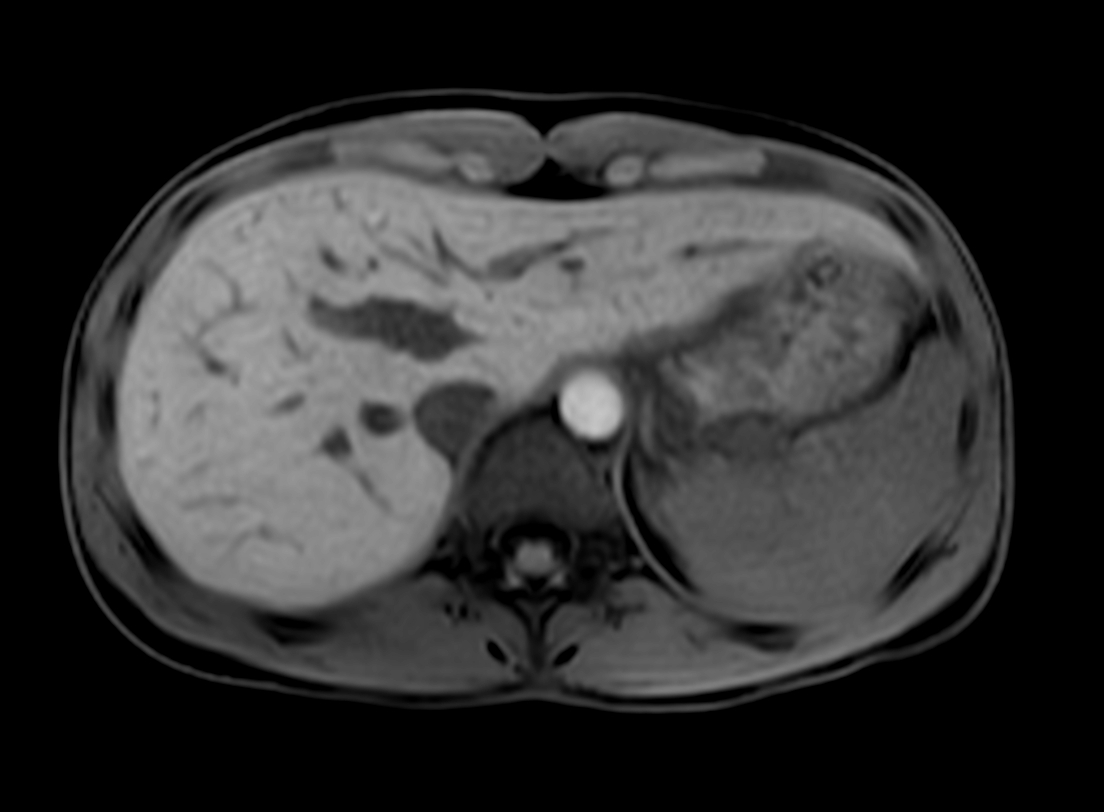

Axial mDIXON XD - T1w FFE (Water only)